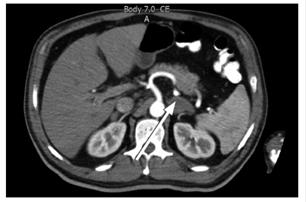

There were no complications related to the procedure (Figure 2). The histopathology report showed necrosis and inflammation. Grocott-Gomori’s (or Gömöri) methenamine silver stain showed aggregations of yeast blastoconidia of varying sizes that were compatible with paracoccidioidomycosis. Ziehl-Neelsen staining was negative for acid-fast bacilli, and no malignancy was observed in the sample (Figures 3 and 4). The patient was treated with amphotericin B until scheme completion and was discharged following evident clinical improvement. Patient continued to have outpatient follow-ups and treatment with itraconazole and oral prednisone.

Figure 3 Hematoxylin-eosin staining shows necrotic tissue (white arrow) in the left adrenal gland and presence of yeast agglomerations (black arrow).